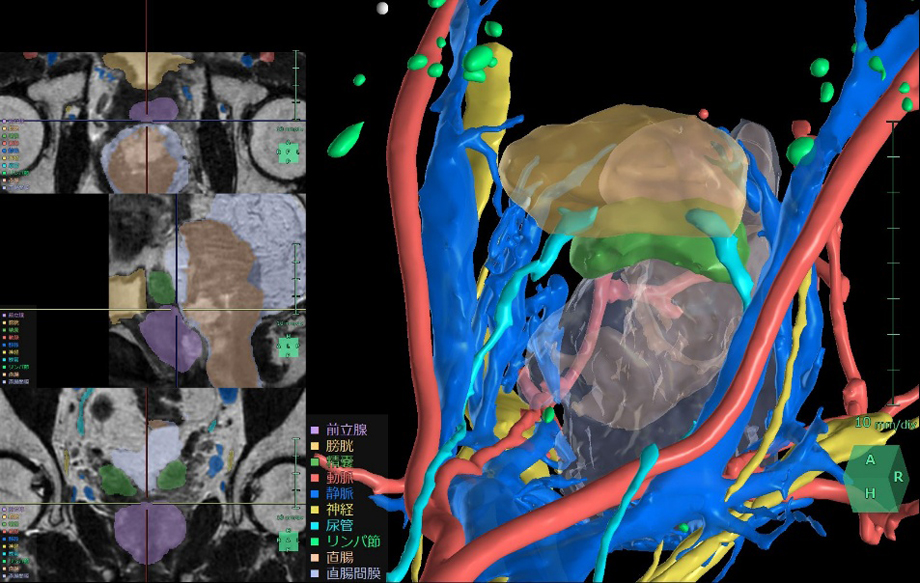

術前のCT画像やMR画像から3D構築を行うことで、骨盤腔内の膀胱周辺臓器や神経、血管の位置関係を把握し、患者ごとに異なる血管走行などの解剖学的特徴を把握し、手術シミュレーションを行うことができる。

すでに解析機能を提供している直腸と同様に、 骨盤内に位置する膀胱や前立腺の手術においても周囲の血管や尿管、臓器の位置関係の把握は非常に重要である。このニーズに対応して、骨盤内の泌尿器科領域に対応したアプリケーション「膀胱周辺臓器解析」を新たにリリースする。この機能により膀胱周囲の臓器や神経、血管の位置把握を支援することで、前立腺癌や膀胱癌手術時のリンパ節郭清等において手術リスクの低減と治療成績の向上への貢献が期待される。